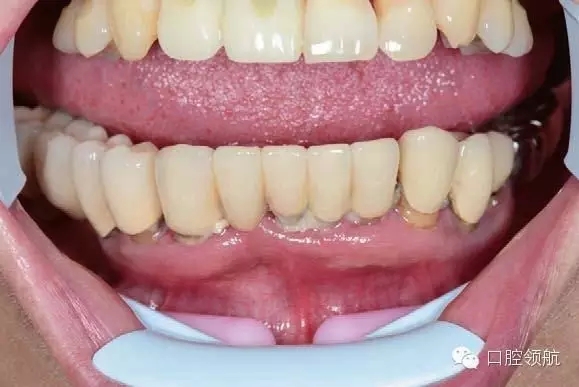

下頜為十?dāng)?shù)年前制作的三組金屬烤瓷橋修復(fù)體。右下4、5、7帶缺失的6;右下3、1及左下1、2帶缺失的右下2;左下3、4、5、8帶缺失的6、7,左下8修復(fù)后牙齒自然脫落,全景片無左下8的影像。幾乎所有的余留牙周圍的骨質(zhì)均吸收到根尖1/3。臨床上三組下頜金屬烤瓷橋均有較大幅度的松動(dòng)(圖6-7,圖6-8)。

圖6-7 術(shù)前口內(nèi)照片